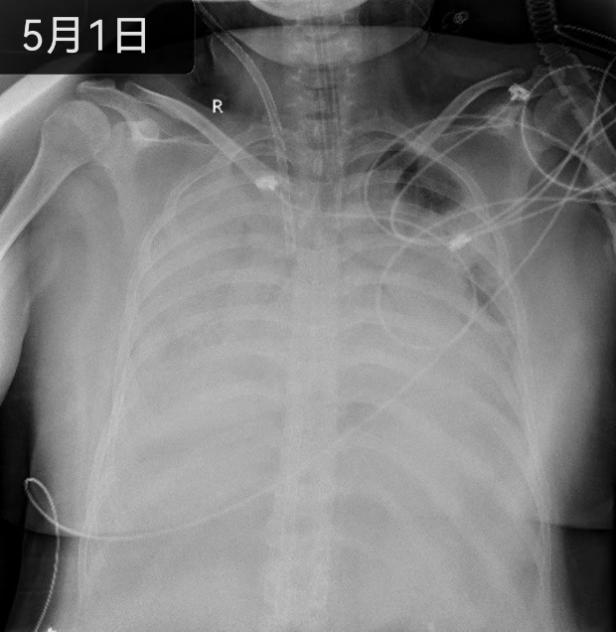

4月的最后一天深夜,呼吸与危重症医学科杨拴盈主任接到来自陕北基层医院的求助电话,希望转诊一名35岁女性患者。该患者既往患有系统性红斑狼疮,曾因狼疮脑病和狼疮肾炎进行激素冲击治疗,长期服用激素和免疫抑制剂,已出现药物相关严重不良反应。更为致命的是2天前患者感染了甲型流感病毒,导致病毒性肺炎,呼吸困难迅速进展,胸片显示双侧“白肺”,属于免疫抑制宿主重症肺炎、ARDS。了解病情后,杨拴盈主任迅速安排RICU医护人员为患者开通绿色通道,准备床单元和呼吸机,患者于深夜紧急送入RICU病房。入院后明宗娟教授、单虎、马玉婉医生立即组织抢救,给予气管插管、镇静镇痛肌松、有创机械通气支持,但彻夜的奋战没能换来病情的平稳,纯氧呼吸支持下指脉氧不足50%,酸中毒难以纠正,呼吸机参数已无调整空间,监护仪持续报警,血气分析的二氧化碳分压一路飙升,患者呼吸循环功能处于崩溃边缘,生命垂危。